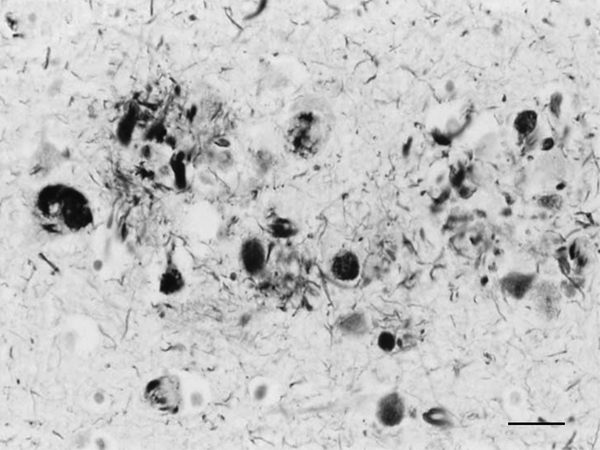

Figure 1: Dystrophic neurites of SPs and NFTs in the frontal cortex of a 76-year-old woman with dementia. Paraffin section, Gros-Bielschowsky silver method without counterstaining, black and white figure, bar = 25μm.

Until the beginning of the last century, cognitive impairment and dementia were considered natural features of old age. Multiple brain infarcts were common in old people, and vascular dementia due to arteriopathy was thought to be the main cause of senile dementia. However, microscopic study of post-mortem brains stained with the dyes available at that time revealed the presence of certain structural anomalies in aged individuals. Paul Block and Georges Marinesco (10) described “amas ronds”, and Emil Redlich (11) “miliare Sklerose” in the neuropil, interpreted at that time as nodules of glial sclerosis, which we now know as senile plaques (SPs). The introduction of the Max Bielschowsky silver method allowed visualisation of argyrophilic structures in neurons. Using this method, Alois Alzheimer described for the first time large numbers of argyrophilic neurofibrillary tangles (NFTs) and aggregates of dystrophic neurites in the brain of a 51-year-old woman who had suffered from progressive dementia and hallucinations in the previous four and half years (12). Other cases were published shortly afterwards (13). The term Alzheimer’s pre-senile dementia was introduced by Emil Kraepelin (14) to define the combination of pre-senile (before the age of 65) dementia in individuals with the morphological lesions described by Alzheimer. Oskar Fischer (15), using the same method, described the presence of ‘Drusen’ or ‘drusige Nekrosen’ in 16 cases of senile dementia characterized by loss of memory and sense of location, disorientation, and confabulation. Subsequent Fischer reports (16, 17) detailed the morphology of abnormal fibrils and abnormal neurites, and their stages of formation, in a large series of older individuals. The term ‘‘senile plaque’’ (SP) for these structures was proposed by Simchowitz (18). Fischer also described “drusige Entartung der Gefässe” which corresponds to amyloid angiopathy. Interestingly, Fischer also reported and illustrated the presence of NFTs in the same cases with dementia (19). Hundreds of articles appeared in the succeeding years. Alzheimer focused on NFTs as the main cause of dementia, whereas Fischer thought that SPs were the main substrate of dementia in older cases. Moreover, Alzheimer contemplated NFTs as aggregates of abnormal neurofibrils, while Fischer considered dystrophic neurites of SPs composed of abnormal neurofibrils, and NFTs a particular abnormality of nerve cells (19). Bielschowsky proposed a link between tangles and neuritic changes (20) (Figures 1 and 2). NFTs and SPs are now considered AD-related pathology or AD-neuropathologic change (ADNC) (https://www.alz.org/media/Documents/alzheimers-facts-and-figures.pdf). The term Pick’s disease (PiD) was coined in 1926 to distinguish AD from PiD primary frontotemporal degenerative atrophy (21). As late as the 1960s, AD and PiD were considered early dementias, whereas pure senile dementia, vascular dementias, and mixed (vascular and degenerative) were classified as dementias in old age (22). The frontiers between AD and pure senile dementia were not clear, as the onset of clinical symptoms in many cases classified as AD was after the age of sixty (23). It was not until the 1970s that Alzheimer’s pre-senile dementia and senile dementia with changes of Alzheimer type were considered to be within the same spectrum (24-27). The inclusive term “Alzheimer-Fischer dementia” was never contemplated.

Electron microscopic studies revealed that NFTs were composed of paired helical filaments (PHFs) that disrupted the architecture of the cyto-skeleton. SPs were forged from a core of compact fibrils consistent with amyloids surrounded by dystrophic neurites filled with altered mitochondria, vesicles, numerous pleomorphic residual bodies, and PHFs (56-61) (Figure 3).